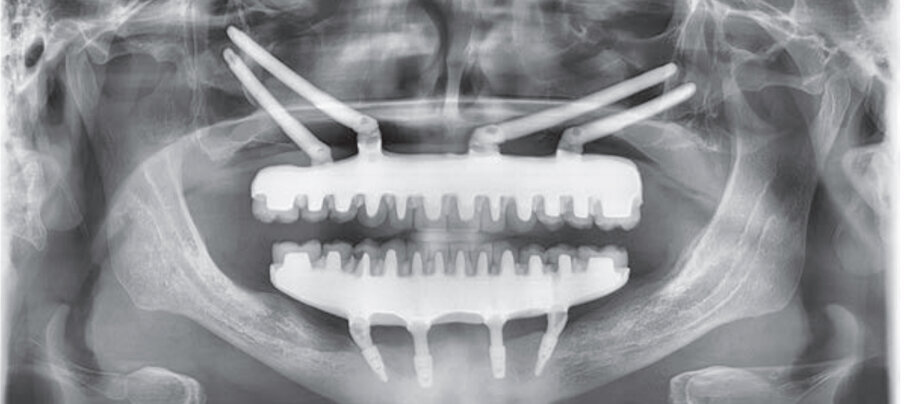

Nel mascellare inferiore si inseriscono 4 impianti Advan GTB (Figg. 6, 7): in posizione 3.5, un impianto inclinato di 3.6x10.5 mm con un multiunit abutment di 4.5 mm inclinato di 30°; in posizione 3.2 un impianto di 3.6x7.5 mm con un multi-unit abutment dritto di 5.5 mm; in posizione 4.2 un impianto di 3.6x7.5 mm con un multi-unit abutment dritto di 6.5 mm; e in posizione 4.5, un impianto inclinato di 3.6x9 mm con un multi-unit abutment di 4.5 mm inclinato di 30°. La profondità sottocrestale degli impianti varia dai 2 ai 3 mm. Lo stesso giorno, si realizza un carico immediato con due protesi avvitate provvisorie in resina. Si controlla il paziente dopo una settimana per la rimozione dei punti di sutura, dopo un mese e dopo 3 mesi e mezzo dall’intervento, momento in cui si realizza una ortopantomografia, si verifica l’osteointegrazione di tutti gli impianti e si prendono le impronte per la fabbricazione delle protesi definitive, consistendo queste ultime in strutture ibride avvitate con un nucleo metallico anatomico e monconizzato, corone singole di disilicato di litio cementate e gengiva artificiale in composito rosa (Fig. 8).

Fig. 9 - Ortopantomografia realizzata dopo la collocazione della protesi definitiva.